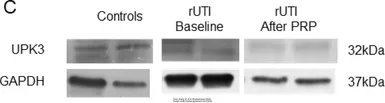

The data was published in the 2021 in Stem Cell Res Ther. PMID: 34020702